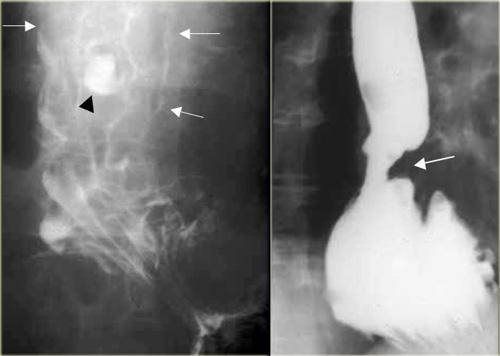

Bên trái là các túi thừa cửa sổ chủ-phổi nhỏ (mũi tên), là phát hiện tình cờ ở hai bệnh nhân.

Ngoài cùng bên trái là túi thừa do kéo (mũi tên) do bệnh u hạt vùng rốn phổi.

Hạch vôi hóa (dấu hoa thị).

Ở giữa là túi thừa do áp lực (mũi tên) do tăng áp lực trong lòng ống.

Bên phải là nhiều túi thừa do áp lực (mũi tên) xuất hiện trước khi thực hiện phẫu thuật cắt cơ Heller điều trị co thắt tâm vị (achalasia).

Bên trái là túi thừa do kéo (mũi tên) thứ phát sau lao hậu nguyên phát.

Hình ảnh này có thể nhầm lẫn với tổn thương phổi dạng hang trên phim X-quang ngực.